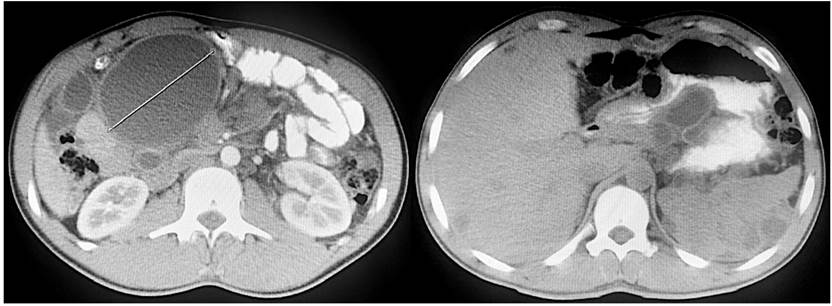

A simple and contrasted abdominal and pelvic tomography was performed. Mild hepatosplenomegaly, simple diffuse-distribution intrahepatic and splenic cysts, mesenteric cysts (also in diffuse form), and dilation of intestinal loops with significant distension of the duodenum (Figure 2) were documented. The results were evaluated by the General Surgery surgical board. Due to findings in imaging studies, it was considered that with unclear etiology, residual collections of previous surgical procedures should be discarded. Exploratory laparotomy should be taken, with cysts resection performed and a pathological study to define the etiology and final behavior.

Figure 2 Simple and contrasted abdominal and pelvic tomography. Axial section showing numerous rounded lesions of liquid content, encapsulated and distributed at the root of the mesentery, liver, spleen, and peritoneum.